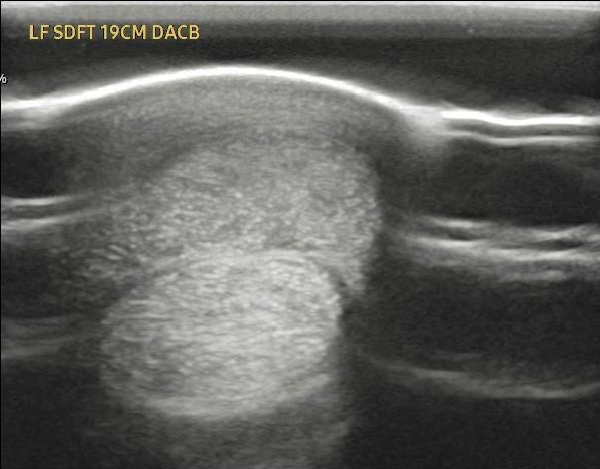

Case Study 1 – Equine Tendon Regeneration

The attached images display a pre- and post-treatment of an equine superficial digital flexor tendon injury, which is roughly the same size as a human Achilles tendon.

A single dose of Tropoflex joint formulation led to a decrease in the core tendon lesion from 91% stenosis to 1.5% stenosis over three months.

Source: Temecula Creek Equine